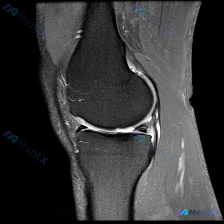

刚看到一个很有代表性的读片病例,临床怀疑膝关节软骨异常,给了单幅膝关节矢状位T2加权MRI,整理一下分析思路分享给大家。

- 影像资料:单幅膝关节矢状位T2加权(或脂肪抑制质子密度加权)MRI,图像质量好,无运动伪影,覆盖股骨远端、胫骨近端、半月板、交叉韧带等主要结构

- 关节软骨:股骨远端、胫骨近端软骨信号均匀,表面轮廓连续,没有看到局灶性剥脱、变薄或异常信号增高,当前层面未见明确结构性软骨异常